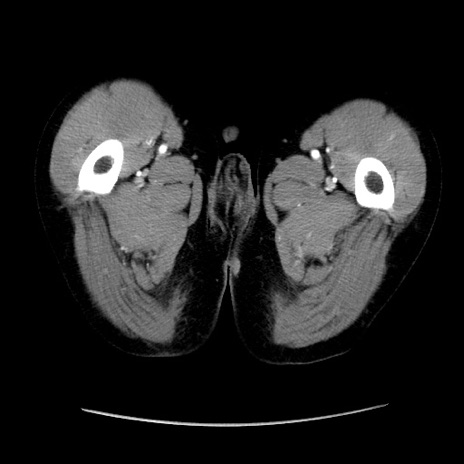

症例37(横断像)

【症例】40歳代 男性

【主訴】腹痛

【現病歴】4時間ほど前に電車に乗車中に臍部上より腹痛出現。徐々に増悪し起立困難となり、救急外来受診。生ものは数日食べていない。今朝お雑煮を食べた。

【身体所見】BT 36.8℃、BP 117/84mmHg、HR 91/min、SpO2 97%、苦悶様、腹部:臍上部広範囲圧痛あり、反跳痛±

【データ】WBC 8100、CRP 0.03